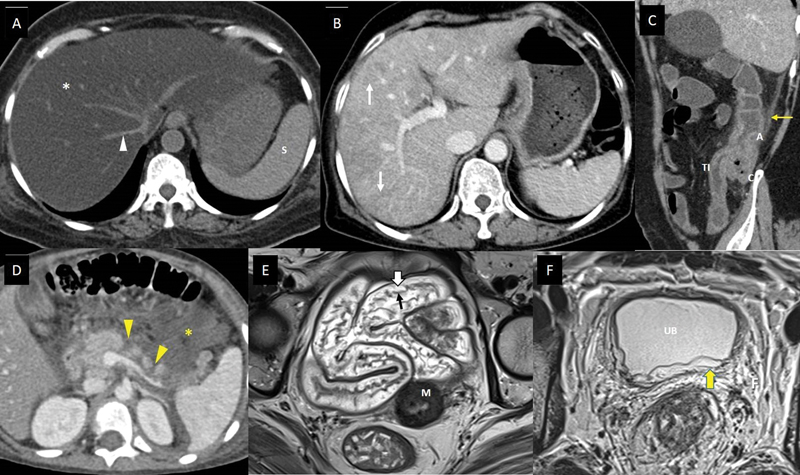

| Figure 3:Imaging features of abdominal complications of cancer therapy. (A) A 53-year-old suffering from acute lymphoblastic leukemia, on treatment with steroids and L-asparaginase, presented with mild abdominal pain and hyperbilirubinemia. Axial noncontrast computed tomography (CT) scan shows markedly reduced density of the entire hepatic parenchyma (white asterisk), suggesting fatty liver. The vessels (white arrowhead) and spleen (S) appear hyperdense to hepatic parenchyma in this noncontrast phase of CT scan due to diffuse fatty infiltration. (B) A 61-year-old lady with metastatic carcinoma stomach, on treatment with oxaliplatin. Axial CT scan of the abdomen with intravenous (IV) contrast done after few cycles of chemotherapy shows heterogeneous enhancement of the hepatic parenchyma with linear hypodensitites (white arrows), which is new compared to the baseline CT scan done 3 months back, suggesting oxaliplatin-induced sinusoidal obstruction syndrome. (C) A 48-year-old man with lung adenocarcinoma, treated with pembrolizumab and carboplatin, presented to the emergency department (ED) complaining of abdominal pain, multiple episodes of diarrhea, and vomiting 6 days after a chemotherapy cycle. Sagittal CT scan of the abdomen with IV contrast shows thickened and edematous wall of ascending colon (A), caecum (C), and terminal ileum (TI), with surrounding fat stranding (yellow arrow), and maintained mural stratification. The patient was found to be severely neutropenic, and these imaging findings along with the clinical presentation, suggested neutropenic enterocolitis/typhlitis. (D) A 6-year-old boy suffering from acute lymphoblastic leukemia, on treatment regimen containing L-asparaginase, presented to the ED with acute abdominal pain and vomiting. He was found to be hypotensive and serum amylase and lipase were raised. Axial CT scan of the abdomen with IV contrast shows nonenhancing areas within the pancreatic parenchyma indicating necrosis (yellow arrowheads), and collection in peripancreatic region containing foci of fat (yellow asterisk). The features suggest acute necrotizing pancreatitis with peripancreatic fat necrosis. (E) A 47-year-old lady receiving radiation therapy for carcinoma of the cervix uteri, underwent response assessment magnetic resonance imaging (MRI) after 20 fractions along with cisplatin. Axial T2-weighted MR image shows submucosal edema as hyperintense signals (white block arrow) deep to the hypointense mucosal layer (black arrow), and maintained mural stratification, involving pelvic small bowel loops, indicating radiation-induced enteritis. The tumor with posttreatment changes is seen involving the cervix (M). (F) A 32-year-old man with rectal adenocarcinoma, underwent a response assessment MRI after neoadjuvant chemoradiotherapy. He complained of mild lower urinary tract symptoms. Axial T2-weighted MR image shows edematous wall of urinary bladder (UB), with hyperintense signals involving the submucosa and muscularis (yellow block arrow), and surrounding edematous pelvic fat (F). The features suggested radiation-induced cystitis.

| Figure 3:Imaging features of abdominal complications of cancer therapy. (A) A 53-year-old suffering from acute lymphoblastic leukemia, on treatment with steroids and L-asparaginase, presented with mild abdominal pain and hyperbilirubinemia. Axial noncontrast computed tomography (CT) scan shows markedly reduced density of the entire hepatic parenchyma (white asterisk), suggesting fatty liver. The vessels (white arrowhead) and spleen (S) appear hyperdense to hepatic parenchyma in this noncontrast phase of CT scan due to diffuse fatty infiltration. (B) A 61-year-old lady with metastatic carcinoma stomach, on treatment with oxaliplatin. Axial CT scan of the abdomen with intravenous (IV) contrast done after few cycles of chemotherapy shows heterogeneous enhancement of the hepatic parenchyma with linear hypodensitites (white arrows), which is new compared to the baseline CT scan done 3 months back, suggesting oxaliplatin-induced sinusoidal obstruction syndrome. (C) A 48-year-old man with lung adenocarcinoma, treated with pembrolizumab and carboplatin, presented to the emergency department (ED) complaining of abdominal pain, multiple episodes of diarrhea, and vomiting 6 days after a chemotherapy cycle. Sagittal CT scan of the abdomen with IV contrast shows thickened and edematous wall of ascending colon (A), caecum (C), and terminal ileum (TI), with surrounding fat stranding (yellow arrow), and maintained mural stratification. The patient was found to be severely neutropenic, and these imaging findings along with the clinical presentation, suggested neutropenic enterocolitis/typhlitis. (D) A 6-year-old boy suffering from acute lymphoblastic leukemia, on treatment regimen containing L-asparaginase, presented to the ED with acute abdominal pain and vomiting. He was found to be hypotensive and serum amylase and lipase were raised. Axial CT scan of the abdomen with IV contrast shows nonenhancing areas within the pancreatic parenchyma indicating necrosis (yellow arrowheads), and collection in peripancreatic region containing foci of fat (yellow asterisk). The features suggest acute necrotizing pancreatitis with peripancreatic fat necrosis. (E) A 47-year-old lady receiving radiation therapy for carcinoma of the cervix uteri, underwent response assessment magnetic resonance imaging (MRI) after 20 fractions along with cisplatin. Axial T2-weighted MR image shows submucosal edema as hyperintense signals (white block arrow) deep to the hypointense mucosal layer (black arrow), and maintained mural stratification, involving pelvic small bowel loops, indicating radiation-induced enteritis. The tumor with posttreatment changes is seen involving the cervix (M). (F) A 32-year-old man with rectal adenocarcinoma, underwent a response assessment MRI after neoadjuvant chemoradiotherapy. He complained of mild lower urinary tract symptoms. Axial T2-weighted MR image shows edematous wall of urinary bladder (UB), with hyperintense signals involving the submucosa and muscularis (yellow block arrow), and surrounding edematous pelvic fat (F). The features suggested radiation-induced cystitis.